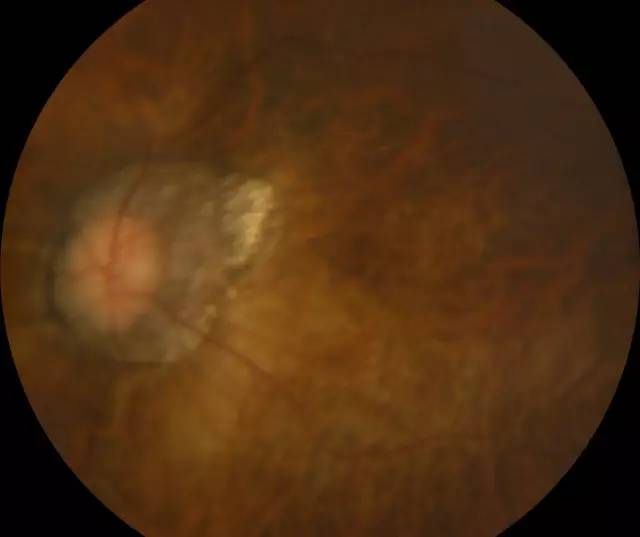

二天,赶上周末,家人陪着肖先生连忙赶到深圳易游体育进行诊治。经过一系列检查,确诊肖先生为超高度近视裂孔性视网膜脱离,由于黄斑区视网膜全部脱离,必须要尽快做手术。

肖先生左眼术前眼底照相图